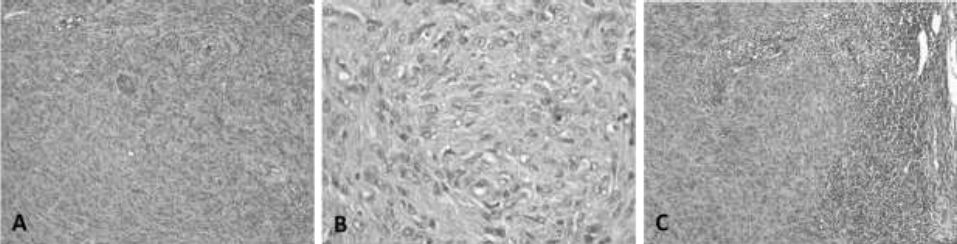

In the tumoral mass, numerous spindle-shaped neoplastic cells were observed, which were arranged in short intertwined bundles (Verocay’s bodies), supported and delimited by fibrovascular stroma (Figure 1, A). In other parts, there were extensive areas of granular eosinophilic material and few fusiform cells (histological pattern Antoni A and Antoni B) (Musha et al., 2018; Salazar et al., 2016).

The cells were fusiform, with poorly defined cell borders, moderate loose cytoplasm, central oval nucleus with sharp edges, granular thick chromatin, and moderate anisocytosis, anisokaryosis, and kariomegaly (Figure 1, B), and fourty three mitotic figures was counted in 2.37 mm2 in the periphery of the tumor in the area with the most mitotic activity. Extensive areas of coagulative necrosis, hemorrhage, and lymphocyte and neutrophil clusters were observed between the cells. The lymphatic vessels were seen distended by clusters of fusiform neoplastic cells. These findings were indicative of a malignant neurilemmoma (schwannoma) grade III (high degree of malignancy) (Ahmadi et al., 2012; Sharif et al., 2017).

General appearanceof tumor:

A. The neoplastic cells, spindle-shaped, are arranged in short bundles (Verocay´s bodies), oriented in the three planes of space and supported by a fibrovascular stroma, relatively scarce.

B. 400X. Details of tumor cellularity. The cells are fusiform, with poorly defined cell borders, central oval nucleus, with thick granular chromatin and moderate anisocytosis, anisokaryosis and kariomegaly. C. 100X. Metastasis to regional lymphonode: The neoplastic tissue occupies the cortex and partially the medulla of lymphonode.

Figure 1 Neurilemmoma. Canine, Shar-pei, male, 4 years. H-E. A. 100X.

In the regional lymph node, there was a depletion of lymphoid cells, observing 60% of lymphoblasts, 15% mature lymphocytes, 15% plasmatic cells, and 10% of macrophages. The medullary sinuses revealed dense clusters of fusiform cells that replaced a large part of the parenchyma of the lymph node, with a very thin cortex and without the characteristic presence of lymphoid nodules (Figure 1, B). These findings corresponded to lymphatic permeation and metastasis to axillary nodes (Ahmadi et al., 2012).